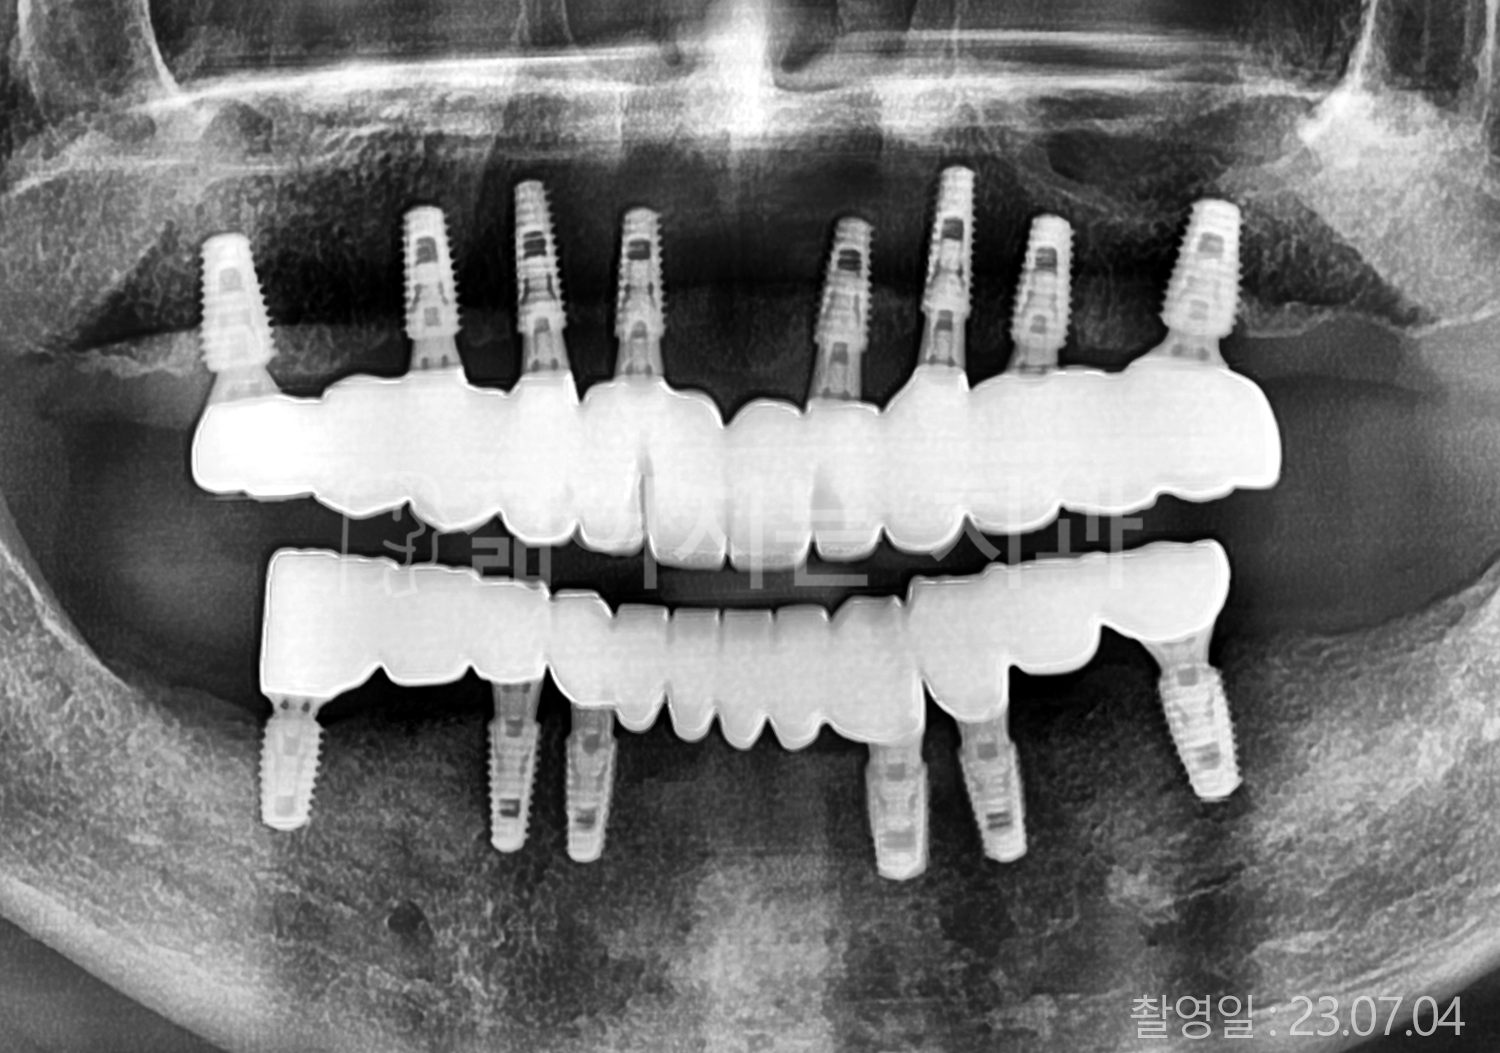

• 50대 고혈압, 당뇨, 고지혈증 전체치아 10개 이상 임플란트

• 60대 골다골증, 간경화 전체치아 10개 이상 임플란트

• 60대 고혈압, 고지혈증 전체치아 10개 이상 임플란트

• 50대 고혈압, 당뇨 전체치아 10개 이상 임플란트

• 60대 고혈압 전체치아 10개 이상 임플란트

• 60대 전체치아 10개 이상 임플란트

• 60대 고지혈증 전체치아 10개 이상 임플란트

• 40대 전체치아 10개 이상 임플란트

• 70대 전체치아 10개 이상 임플란트